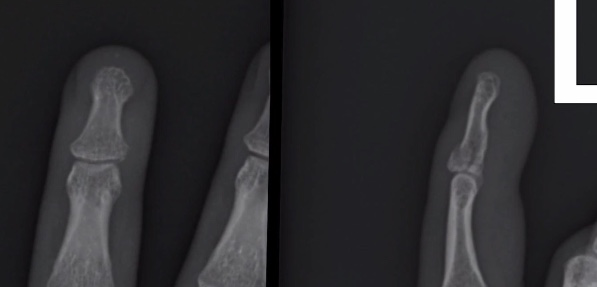

Fracture dorsale d’avulsion de l’IPD

- Le doigt se déforme en Maillet et reste en flexion

Fracture palmaire d’avulsion de l’IPD

- “Jersey finger” (en atrappant le Jersey d’un rugbyman qui court)